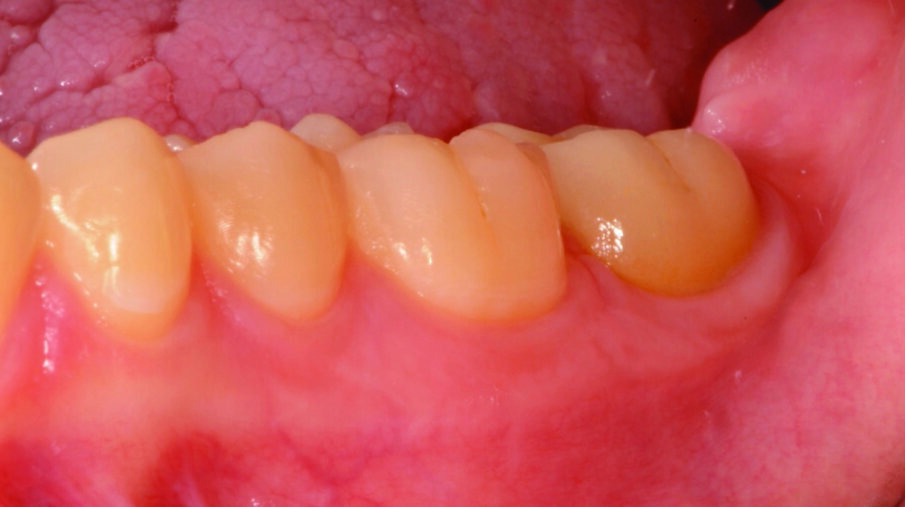

Fig. 5: Tooth preparation after removal of the temporary restoration and mechanical cleaning of the tooth (e.g. pumice paste). Note the healthy gingiva.